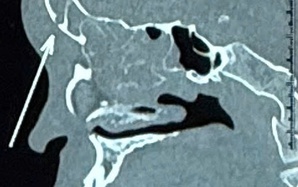

Viêm xoang bướm do nấm âm thầm tấn công người bệnh

(NLĐO ) - Bệnh viêm xoang bướm do nấm có triệu chứng mơ hồ, không điển hình, dễ nhầm với viêm xoang mạn thông thường.